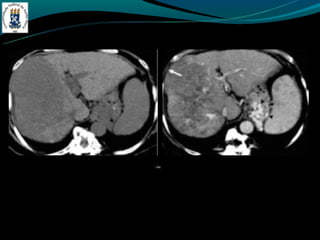

-   TC: densidade menor do que do baço

-   RM: identificar esteatose focal

-Esteatose focal

-   Distribuição segmentar, sub capsular, VB, lig falciforme

-   Margem nítida e em linha reta

-   Não desloca vasos

DOENÇA DO FÍGADOGORDUROSO -E uma resposta uma lesão e a toxina -Acúmulo de colesterol e triglicerídios -Alcoolismo, obesidade, desnutrição, hiperalimentação, costicóide, DM, pancreatite … -Exames de imagem é o melhor método -Avaliação: - TC: densidade menor do que do baço - RM: identificar esteatose focal -Esteatose focal - Distribuição segmentar, sub capsular, VB, lig falciforme - Margem nítida e em linha reta - Não desloca vasos